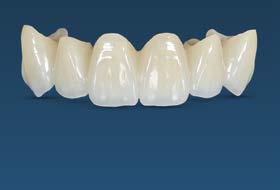

Introducción: el disilicato de litio y el zirconio son de los mejores materiales cerámicos que ofrecen la estética ideal del sector anterior, para la exigencia de los pacientes. Llevar a cabo una correcta toma de color, establecer buena comunicación con el laboratorio y la fase del cementado son factores que buscan lograr un excelente mimetismo con los dientes naturales. Identificar entre estos 2 materiales, cuál ofrece una mejor calidad del color y logrará cumplir los estándares que pide el paciente es crucial. Objetivo: analizar la colorimetría entre 2 materiales cerámicos disilicato de litio y zirconio mediante un reporte de caso clínico. Metodología: experimental comparativo, observacional in vivo en paciente femenino de 56 años, rehabilitado con coronas totales en el sector anterior superior, lado izquierdo con zirconio y lado derecho con disilicato de litio, cementadas con multilink

translucido Ivoclar. Su valoración fue realizada mediante fotografías intraorales con contrastadores negros, en formato RAW, empleando la herramienta de gotero de Adobe Photoshop para la medición del color de ambos cuadrantes superiores. Resultados: las coronas, al ser cementadas, las que fueron confeccionadas con disilicato de litio reportaron tener menos variación del color y el incisivo central reportó menos irregularidad, contra las realizadas de zirconio. Conclusiones: a pesar de usar 2 materiales diferentes, los resultados entre estos son poco significativos. El tener interacción con el paciente sobre el tono deseado final y ser minucioso para el registro del color, serán pasos fundamentales para lograr un buen mimetismo.

Se planteó la utilización de cerámica feldespática e-max de la casa comercial Ivoclar Vivadent, en la presentación de bloques para la realización de las coronas totales en los OD

11, 12 y 13 mediante técnica CAD/ CAM, en su versión HT, color A2. Por otro lado, las otras 2 coronas de los OD 21 y 22 fueron confeccionadas con disco de zirconia Zahndent en tono A2. Estas fueron puestas a prueba mediante la aplicación Adobe Photoshop, con ayuda de una fotografía de las coronas tomada antes de su cementación definitiva, y una segunda medición con las coronas ya cementadas, únicamente se realizó el análisis en los OD 11 Y 21, los cuales fueron cementados con cemento translucido Multilink Speed de Ivoclar Vivadent, se tomaron fotografías con cámara profesional Cannon T8 y lente macro 100mm. Es importante mencionar que decidí utilizar cemento dual translucido para evitar alteración en el color de las coronas ya cementadas, con el fin de obtener mediciones puntuales de color y determinar las cantidades de pigmento que hay en cada corona mediante un fondo negro y así poder corroborar que se logró un buen mimetismo. El tiempo estimado para el procedimiento fue de 5 citas.

Figura 1. Coronas antes de su cementación (Francisco Javier Méndez Landa 2024).

porcentaje de 0 a 100, obteniendo el porcentaje exacto de cada uno de esos colores, que una vez mezclados obtenemos el tono real de las coronas (Figura 1).